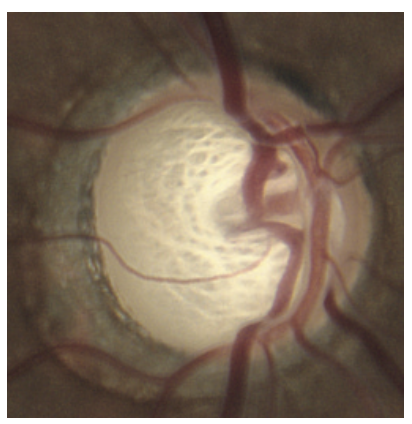

Fundo de olho: Exame do nervo óptico.